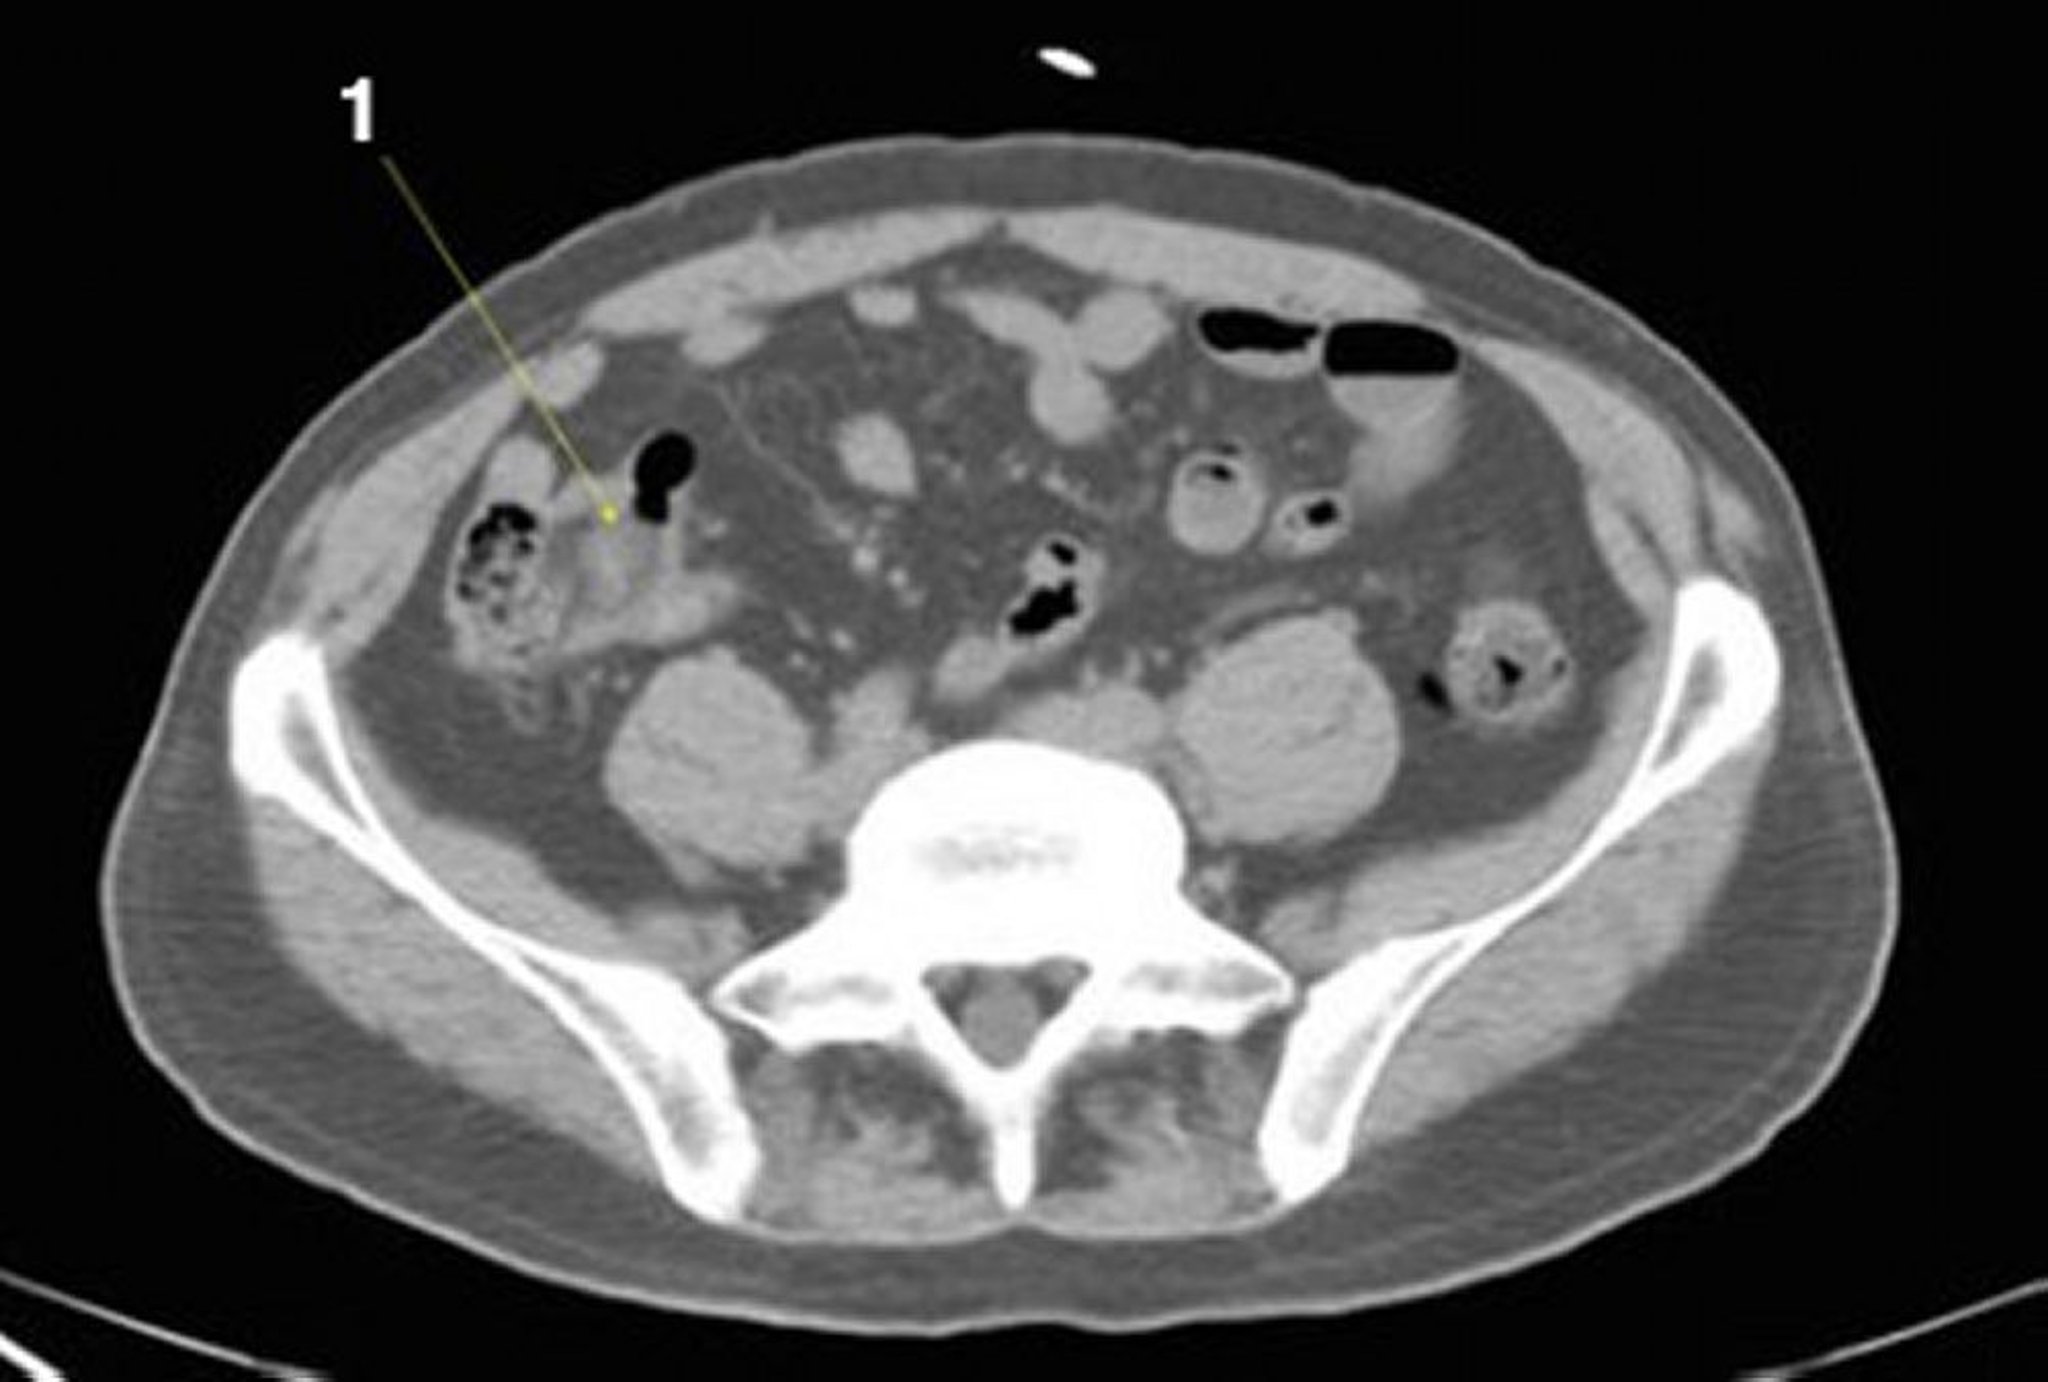

Kontrastmittel CT Abdomen DocCheck Wie aussagekräftig ist ein CT ohne Kontrastmittel? Ohne Kontrastmittel sind bildgebende Verfahren oft nur wenig aussagekräftig Ist ein CT-Kopf ohne Kontrastmittel aussagekräftig? Selbst ohne Kontrastmittel kann eine Computertomografie nützliche Informationen liefern Was ist eine CT-Abdomen? Eine Abdomen-CT (Computertomographie des Bauches und Beckens) ist die mittels Röntgenstrahlen erfolgende Untersuchung des Bauchraumes

Source: notedkoijkf.pages.dev ImageCTScan von Abdomen und Becken mit normaler Anatomie ohne Kontrastmittel (Folie 21)MSD , Zur Untersuchung wird daher auch immer ein Kontrastmittel verabreicht Ein Abdomen-CT wird zur Diagnose und Überwachung einer Vielzahl von Zuständen eingesetzt

Source: plakamqxk.pages.dev Normales AbdomenCT Kenhub , Die Abdomen-CT dient bei einer Vielzahl medizinischer Fragestellungen als wichtiges Instrument der Diagnostik.Sie erfolgt in einer großen Röhre, in der schichtweise Aufnahmen des Bereichs angefertigt und anschließend im Computer zu. Intravenös verabreichte Kontrastmittel werden in der Regel bei CT-Untersuchungen von Lunge (Thorax) und Bauchraum (Abdomen) sowie gelegentlich bei Kopf-CTs eingesetzt.